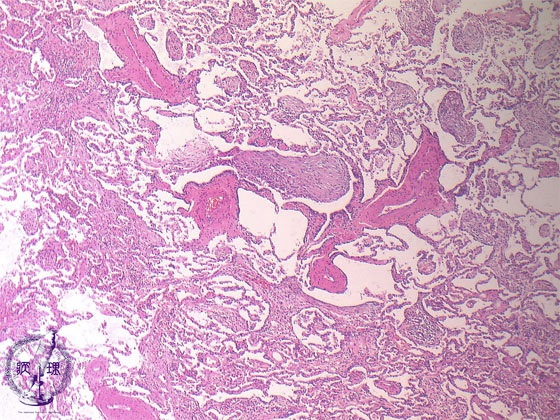

• (12)Interstitial pneumonia(cryptogenic organizing pneumonia (COP)/ Bronchiolitis obliterans organizing pneumonia (BOOP))

Microscopic view (HE stain, low power view): Polypoid granulation tissue fills alveolar ducts and spaces. Lymphocytes are seen infiltrating the interalveolar septum and surrounding bronchioles.